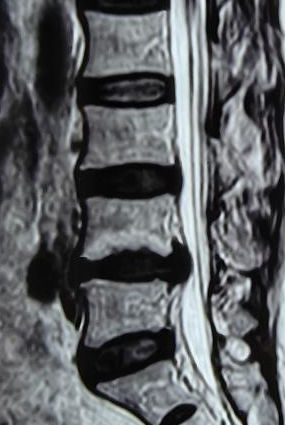

什么是腰椎间盘突出症?

腰椎间盘突出治疗

椎间孔镜手术是什么?